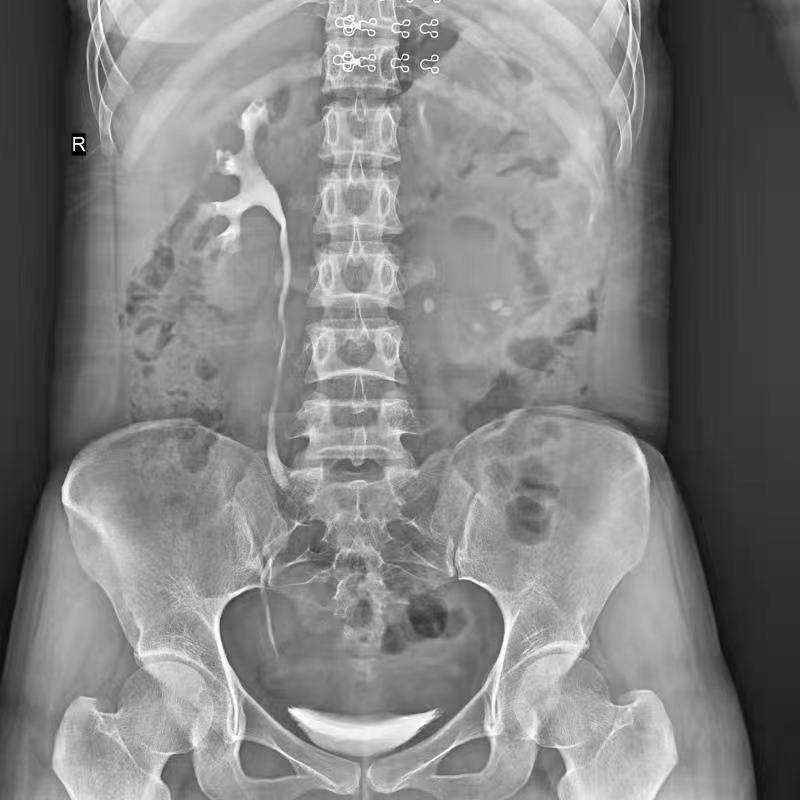

普利德醫(yī)療自主研發(fā)的新一代數(shù)字化X線透視攝影系統(tǒng),可應用于DR攝影、數(shù)字透視、數(shù)字造影以及可視化精準DR拍片等多種臨床X線檢查領域。

拉伸自如:SID電動拉伸,最長可延伸至1.8米,滿足放射科室各種拍片距離的需求。如:GBZ 70-2015職業(yè)性塵肺病的診斷標準中對胸片拍片距離1.8米的要求。

點片裝置移動范圍大,無需患者移動就能完成全身各部位的檢查;

床面橫向移動,輕松實現(xiàn)機動人不動。